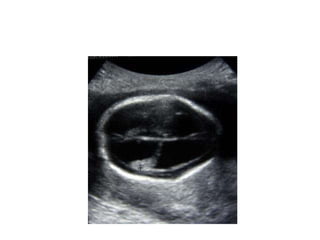

Investigation U ltrasonography to visualize the ventricular system(when the anterior fontanelle is patent). Also for antenatal diagnosis CT and /or MRI of the head; it is important to exclude any abnormal masses and to study the size and the shape of the ventricles, and some time needs contrast study.  LP in cases of communicating hydrocephalus for both diagnostic and therapeutic…..( NPH)

Investigation U ltrasonographyto visualize the ventricular system(when the anterior fontanelle is patent). Also for antenatal diagnosis CT and /or MRI of the head; it is important to exclude any abnormal masses and to study the size and the shape of the ventricles, and some time needs contrast study. LP in cases of communicating hydrocephalus for both diagnostic and therapeutic…..( NPH)